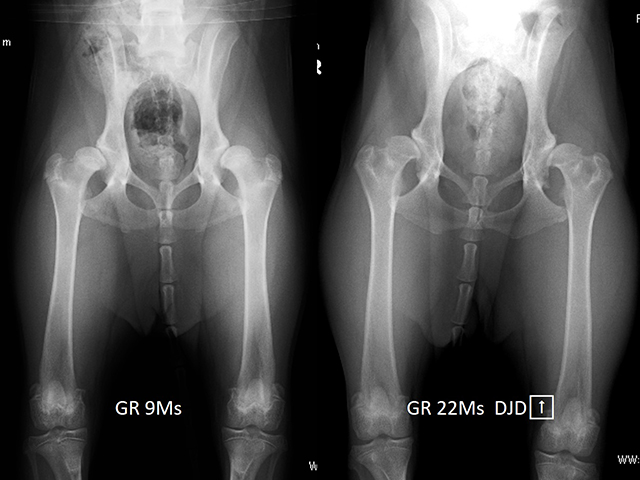

股関節形成不全Hip Displasia

イヌの股関節形成不全は、股関節の緩みや関節炎の原因となる遺伝的疾患です。正常な股関節は、骨盤側の寛骨臼と大腿骨側の大腿骨頭とがしっかりと連結した球状関節を形成しますが、股関節形成不全の場合ではこの連結は次第に緩み、部分的変位または亜脱臼を示すようになります。亜脱臼は、後に関節炎や形成異常の原因となります。